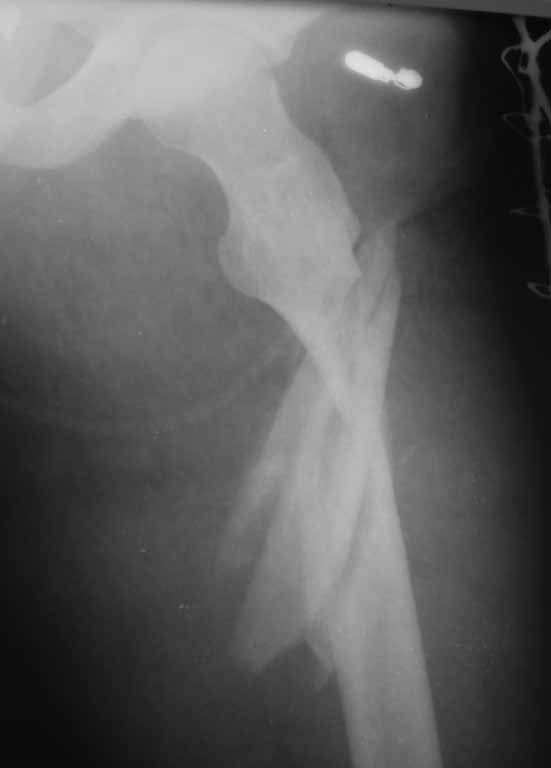

Уважаемые коллеги!!! Ваши предложения по тактике лечения, планируется закрытая репозиция, ИМОС AFN, кто встречался с подобным, какие могут быть сложности интраоперационно

Подвертельный оскольчатый перелом. Если пострадавший относительно молод, нет остеопороза, лучше реконструкционный гвоздь. Успешная репозиция очень важна. С помощь тракционного стола или дистрактора таз-бедро она легко достигается. Остаточный варус - самая распространенная ошибка. Точка входа не должна быть слишком латеральной, даже если гвоздь с проксимальным изгибом. Гвоздь должен идти близко к латеральной стенке центрального отломка.

Аналогичный перелом, синтезировали длинной Гаммой stryker, точка введения через верхушку вертела удобней и безопасней, чем у AFN.